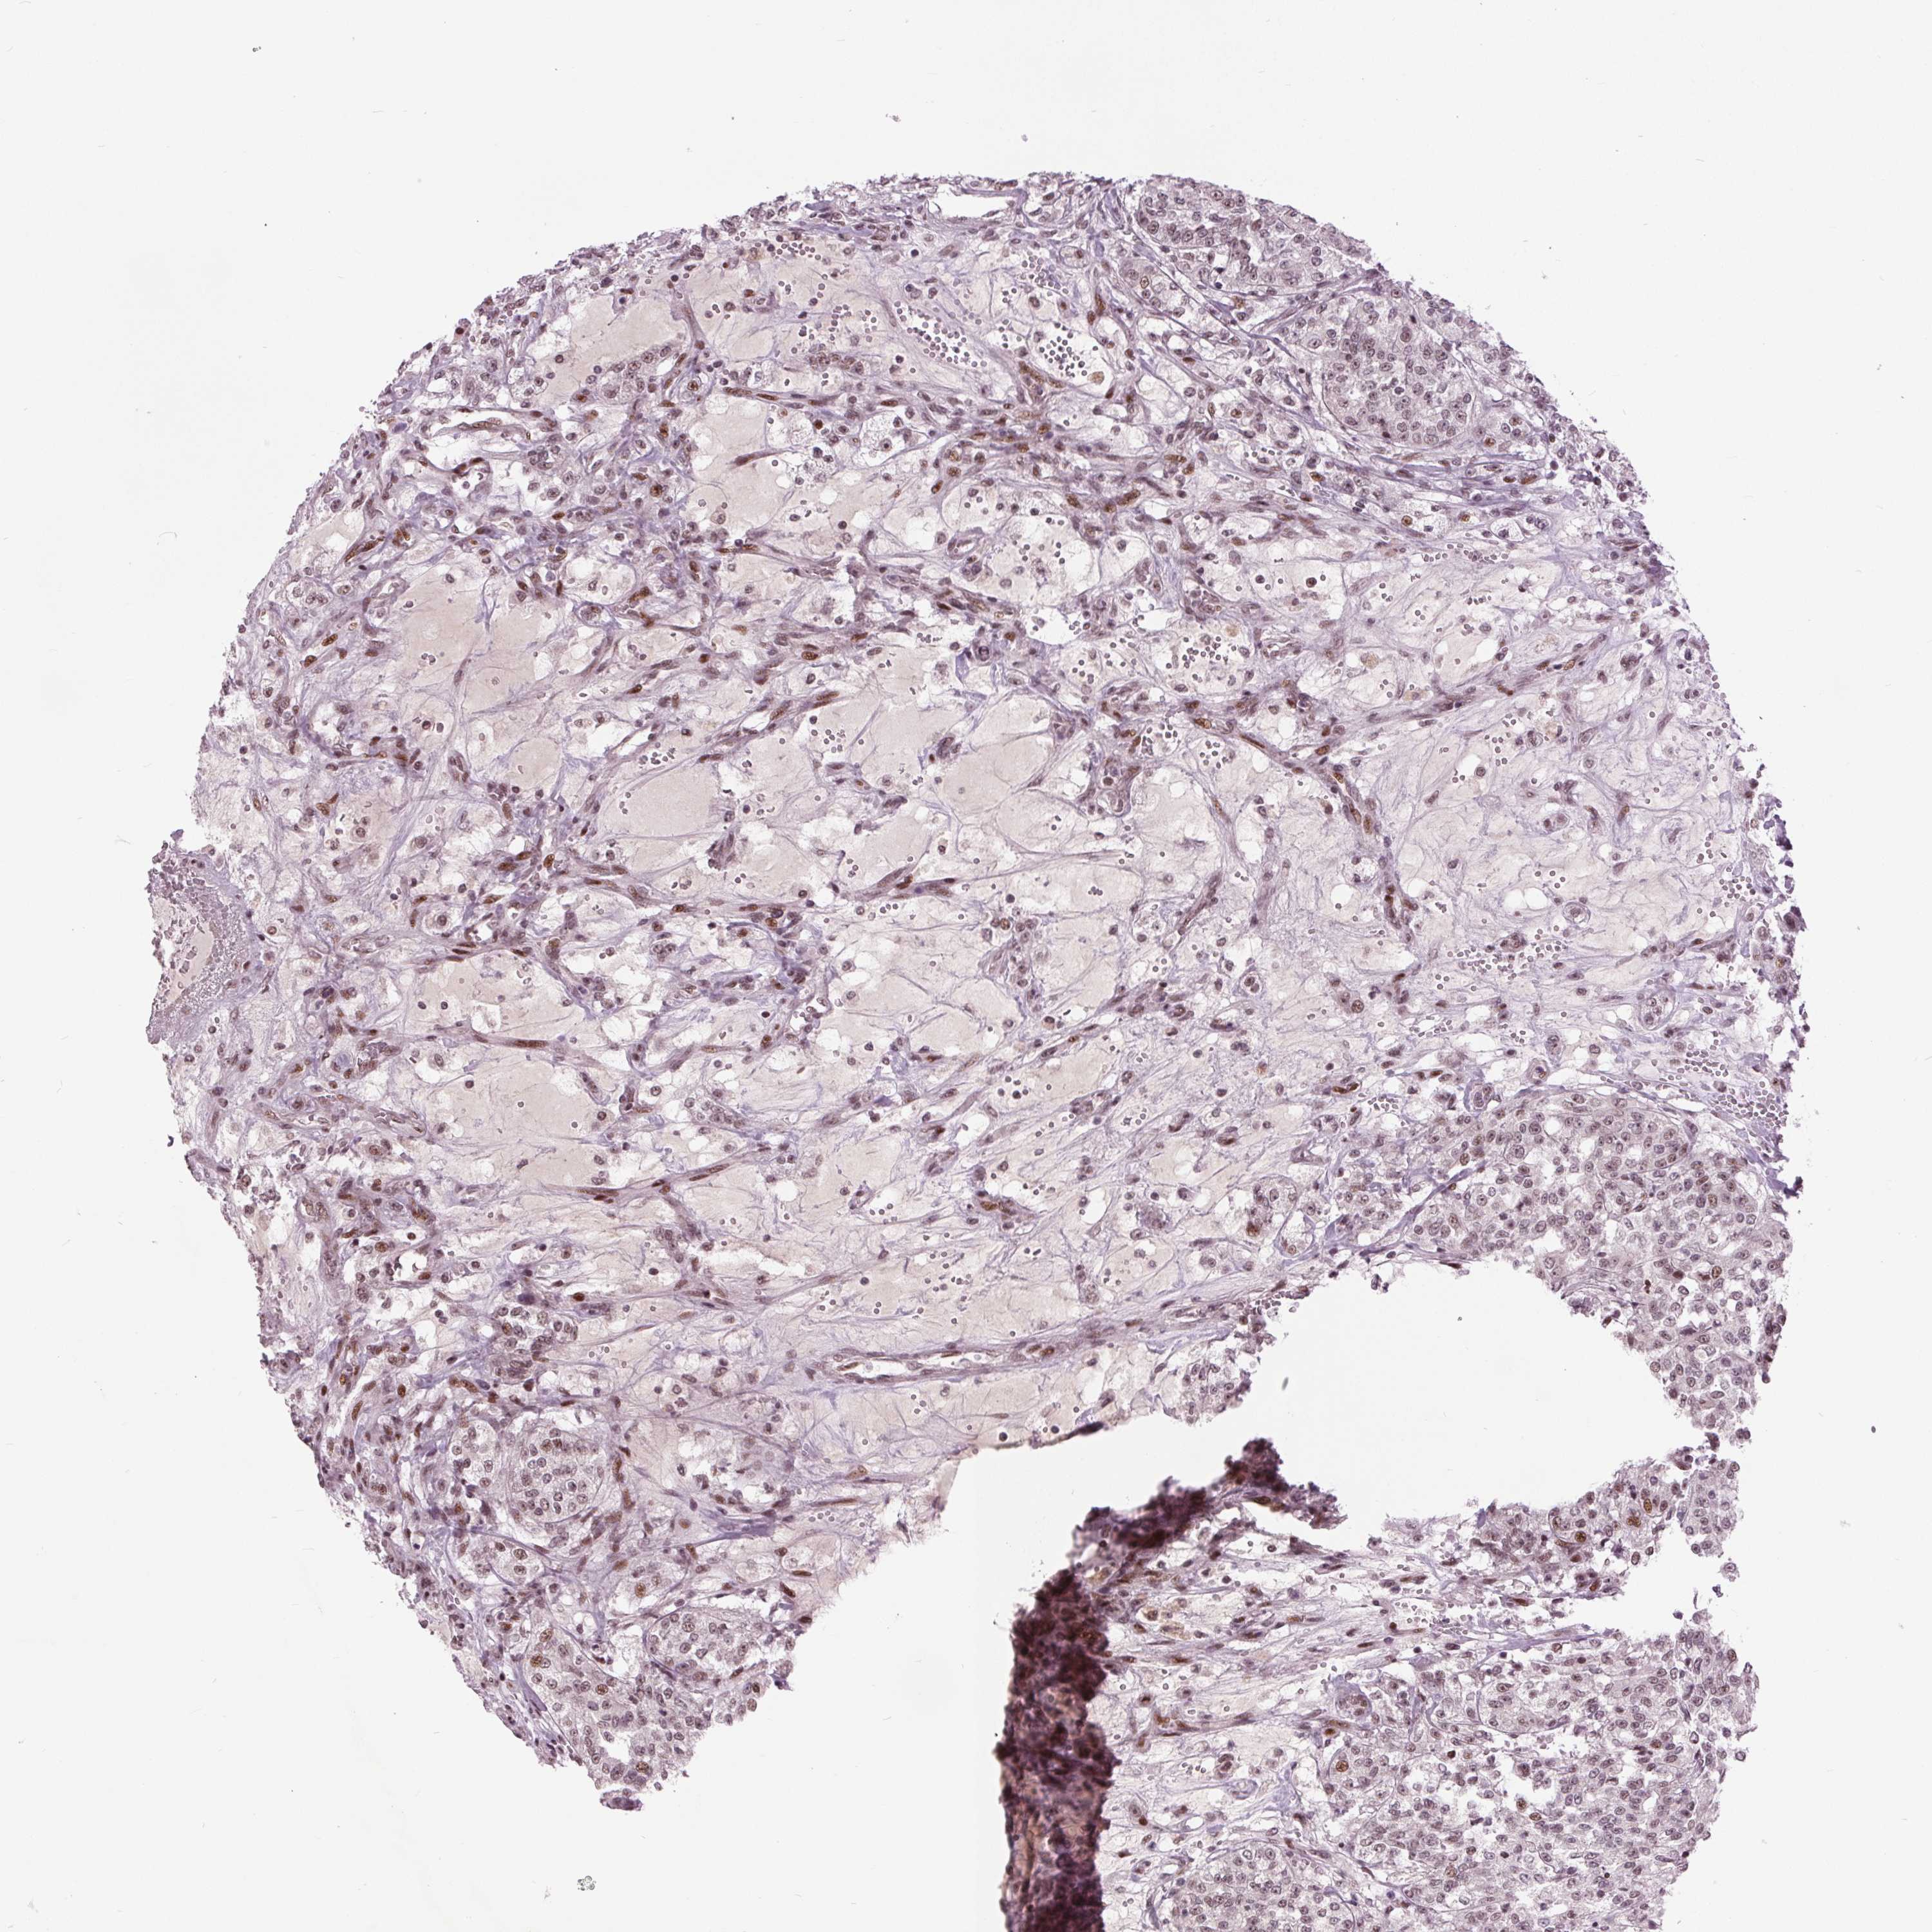

KIDNEY RENAL CLEAR CELL CARCINOMA (VALIDATION) - Interactive survival scatter ploti

The Survival Scatter plot shows the clinical status (i.e. dead or alive) for all individuals in the patient cohort, based on the same data that underlies the corresponding Kaplan-Meier plots. Patients that are alive at last time for follow-up are shown in blue and patients who have died during the study are shown in red.

The x-axis shows the expression levels (FPKM) of the investigated gene in the tumor tissue at the time of diagnosis. The y-axis shows the follow-up time after diagnosis (years). Both axes are complimented with kernel density curves demonstrating the data density over the axes. The top density plot shows the expression levels (FPKM) distribution among dead (red) and alive patients (blue). The right density plot shows the data density of the survived years of dead patients with high and low expression levels respectively, stratified using the cutoff indicated by the vertical dashed line through the Survival Scatter plot. This cutoff is automatically defined based on the FPKM cutoff that minimizes the p-score. The cutoff can be changed by dragging the vertical line or by entering a cutoff value in the square labeled "Current cut-off".

Under the Survival Scatter plot the p-score landscape (black curve; left axis) is shown together with dead median separation (red curve; right axis). Dead median separation is the difference in median mRNA expression between patients who have died with high and low expression, respectively. It is calculated as follows: median FPKM expression of dead patients with high expression - median FPKM expression of dead patients with low expression. This is intended to aid the user in visually exploring custom cutoffs and the associated p-scores and dead median separation.

Individual patient data is displayed and can be filtered by clicking on one or more of the category buttons on the top of the page. Categories describing expression level and patient information include: high, low, alive, dead, female, male and tumor stages. The scale of the x-axis can be toggled between linear and log-scale by clicking on the "x log" button. Mouse-over function shows TCGA ID, patient information and mRNA expression (FPKM) for each patient.

& Survival analysisi

Kaplan-Meier plots summarize results from analysis of correlation between mRNA expression level and patient survival. Patients were divided based on level of expression into one of the two groups "low" (under cut off) or "high" (over cut off). X-axis shows time for survival (years) and y-axis shows the probability of survival, where 1.0 corresponds to 100 percent.

TTC34 is not prognostic in Kidney Renal Clear Cell Carcinoma (validation)

TCGA RNA samplesi

RNA-seq data is reported as average FPKM (number Fragments Per Kilobase of exon per Million reads), generated by the The Cancer Genome Atlas (TCGA) .

Normal distribution across the dataset is visualized with box plots, shown as median and 25th and 75th percentiles. Points are displayed as outliers if they are above or below 1.5 times the interquartile range. FPKM values of the individual samples are presented next to the box plot.

Average pTPM 0.3

Number of samples 100